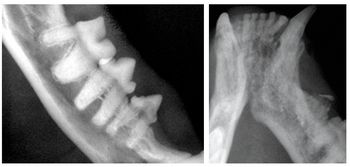

Practical knowledge of veterinary dental anatomy and physiology is essential to the veterinarian and veterinary technician involved in providing quality oral care to their patients. Quality surgical skills are only attainable with a thorough understanding of these concepts.

Proper professional dental prophylaxis is a must for every small animal practice. Prevention of periodontal disease can be accomplished only through regular professional care under general anesthesia. The following discussion details the essential steps in providing a thorough dental prophylaxis for our patients.